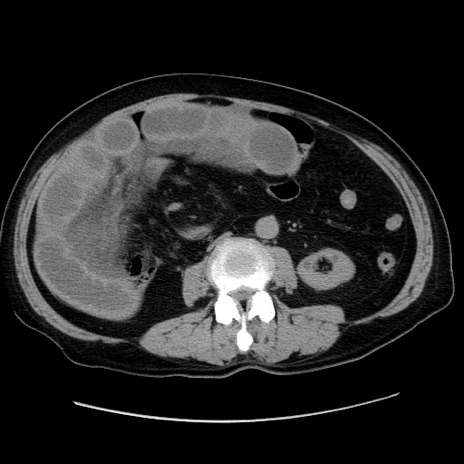

症例30(横断像)

【症例】80歳代男性

【現病歴】約6時間前から臍下部痛が出現。次第に腹部膨隆・背部痛も生じてきたため来院。背部痛の場所は変化しない。

【身体所見】意識清明、BT 36.3℃、BP  131/87mmHg、P 87bpm、SpO2 100%(RA)、臍周囲自発痛・圧痛あり、反跳痛なし、自発痛部位に一致して板状硬あり、腹部膨隆、腸雑音減弱、CVA tenderness両側陰性。

【データ】WBC 19600、CRP 0.33